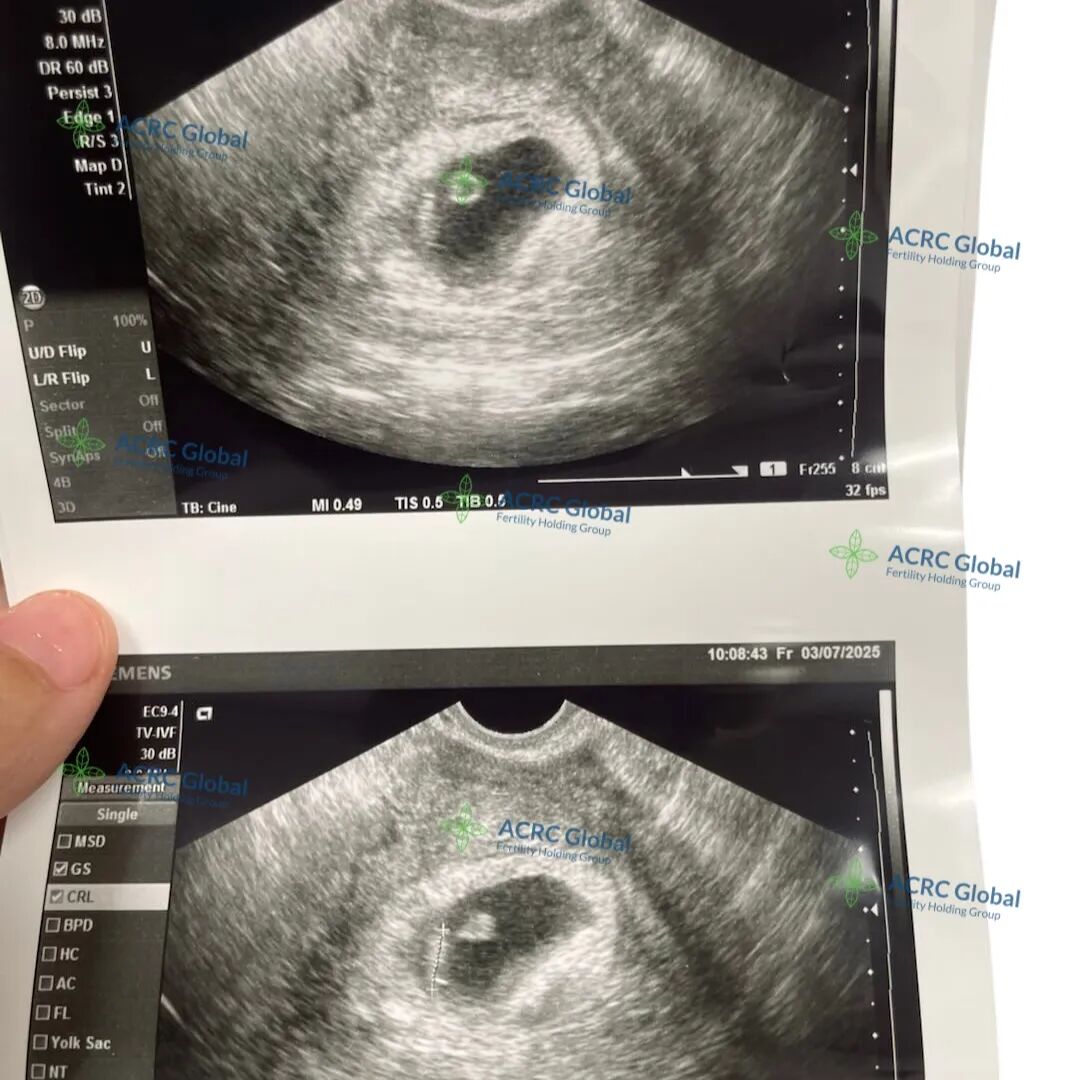

爱妈Y的第二次孕期之旅和上次一样顺利,今天迎来了首次B超检查的好消息宝宝已经成功着床啦!作为一位经验丰富的爱妈,她在上一次孕期中成功帮助准父母迎来了双胎宝宝,这次与一位单身妈妈匹配,对整个流程可谓驾轻就熟,配合度依旧非常高。准妈妈得知这一喜讯后,满怀期待和信心,希望不久的将来,就能迎来属于自己的小天使!

如今首次B超检查传来喜讯——宝宝已经6周,心跳清晰可见! 准父母心情激动不已,他们满怀期待的小生命,正在爱妈M的悉心守护下健康成长。